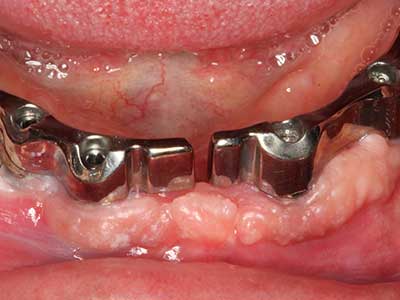

Aplicación: Terapia periodontal

En pacientes de edad avanzada, las enfermedades periodontales marginales representan la razón principal por la que es preciso realizar una extracción. Estas enfermedades tienen principalmente su causa en una colonización bacteriana de la bolsa periodontal y en la inflamación que esta provoca, lo que da lugar a una pérdida del ligamento periodontal. La formación de biopelículas y concreciones subgingivales representa un factor etiológico decisivo para la degradación ósea marginal, por lo que su eliminación cobra una importancia especial en la terapia (Drisko 2014, Plessas 2014).

En el tratamiento de una periodontitis se hace una diferenciación entre la fase inicial y la fase quirúrgica. Además de la instrucción y la motivación entorno a la higiene bucal, en ambas fases debe realizarse una limpieza apropiada de la superficie radicular; a este respecto, en el tratamiento regenerador se elige casi siempre un acceso abierto. La superficie radicular también puede limpiarse mediante piezocirugía utilizando piezas especiales, pues el uso de insertos de diferentes curvaturas permite llegar a zonas de difícil acceso, como son las furcaciones. En esta técnica, la refrigeración interna de agua del sistema ayuda a retirar las concreciones y las bacterias disueltas de la bolsa periodontal. Por otro lado, para reducir a un mínimo la eliminación de la sustancia dental dura, en los sistemas especiales como el Piezomed se ha incorporado una aplicación con retroalimentación. En este caso, según se ejerza más presión sobre la pieza periodontal, la potencia de eliminación se reduce.

Insertos blandos especiales para el tratamiento de la periimplantitis están abriendo nuevas perspectivas en odontología. En la actualidad están siendo objeto de investigación y los resultados iniciales son muy prometedores.